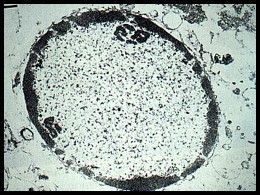

A 55 year old woman with a 10 year history of HIV infection comes to her physician after having trouble moving the left side of her body. She fears she may have had a stroke. Additionally her husband states that her behavior has been strange for the past few months and she has trouble remembering things. A brain biopsy is taken after the MRI fails to reveal an area of ischemia. Based on the histologic sample below (contents of macrophages in neural tissue), what might her diagnosis be?

HIV infection causing neurological changes:

Dementia associated with HIV may be related to actions of cytokines released by macrophages (front) in response to HIV virus infection of these cells.

- HIV in the brain is characterized histologically by the presence of perivascular multinucleated giant cells that have been shown to contain HIV.

Also associated with a vacuolar myelopathy. (below)